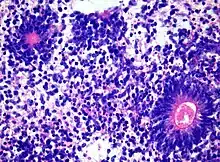

Medulloepithelioma, on the other hand, are tumors involving the constant cell division on the epithelium tissue where bundle of neuron endings are located.[1] Such tissue will differentiate into a similar form as the embryonic neural tube, also known as the starting structure of the central nervous system.[1][2][3] Medulloepitheliomas also present a pattern known as rosettes, characterized by the arrangement of a bundle of cells into circular shapes and around a center or a neuropil.[1] Ependymoblastoma also present rosettes as well as a higher density of cells.[1][3] It involves the process of differentiation into ependymal cells.[2][3]